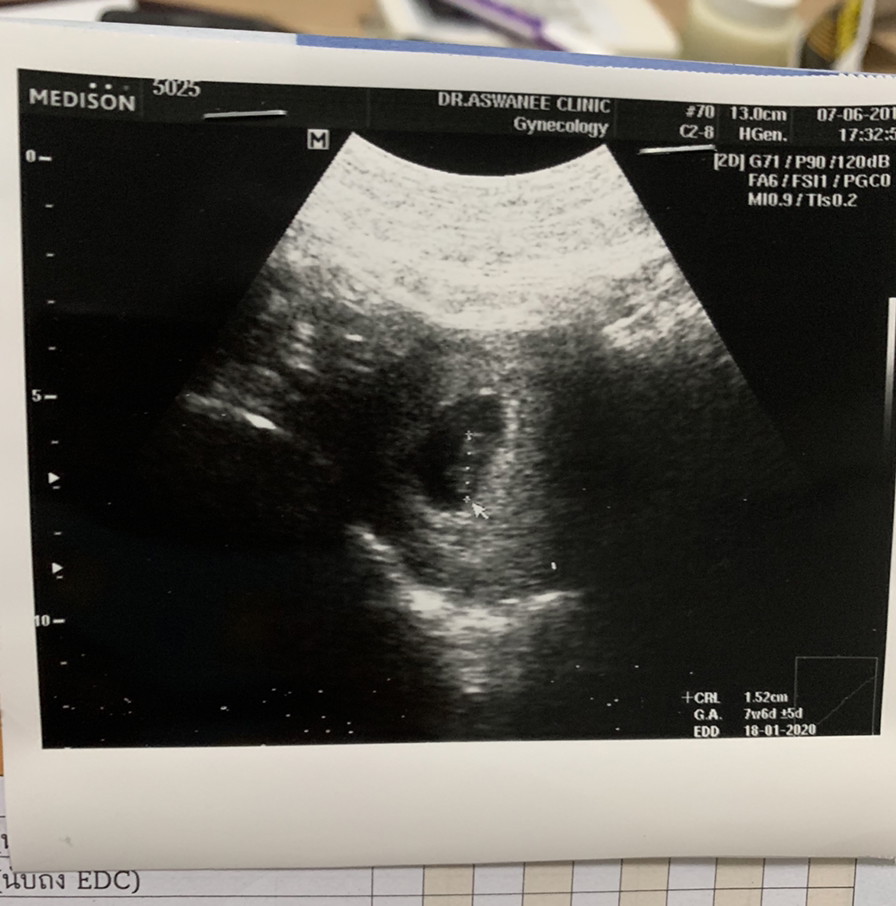

ภาพแรกของหนู ตอนอายุครรภ์ 7W6D